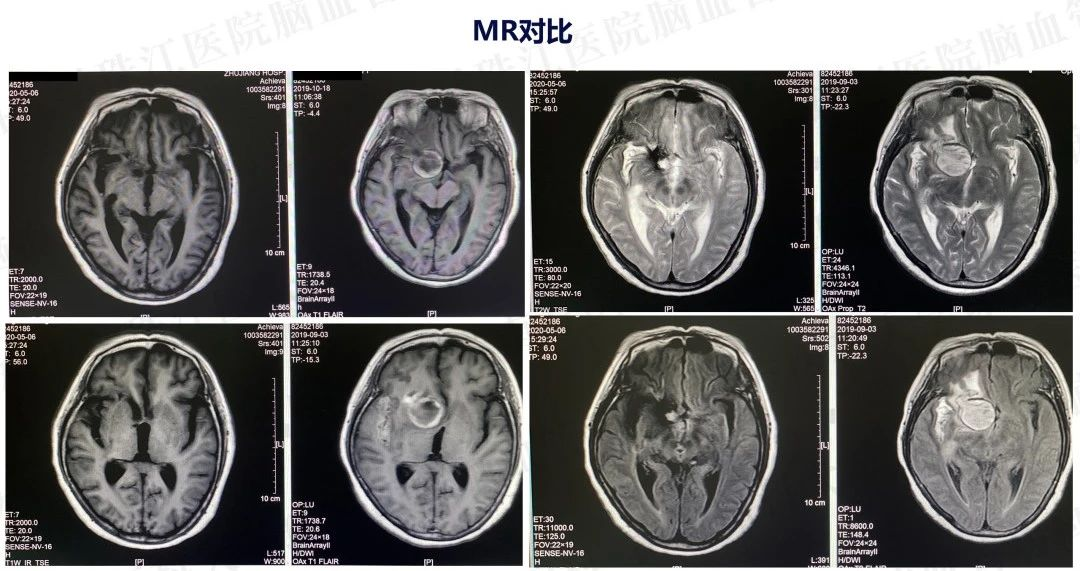

患者入院后造影发现“颈内动脉床突上段巨大动脉瘤,大小约2.7x3.5cm。决定行PIPELINES密网支架植入治疗。

患者入院后造影发现“颈内动脉床突上段巨大动脉瘤,大小约2.7x3.5cm。决定行PIPELINES密网支架植入治疗。